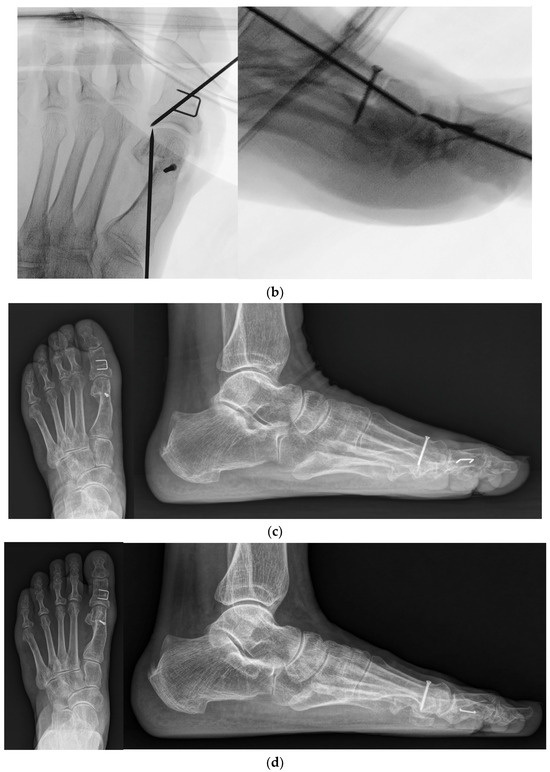

Figure 3.

(a) Preoperative standing foot anteroposterior and lateral radiographs; (b) Intraoperative foot anteroposterior and lateral fluoroscopy images; (c) Standing foot anteroposterior and lateral radiographs at 2 months post operation; (d) Standing foot anteroposterior and lateral radiographs at the final follow-up.

Rehabilitation protocols were as follows: (1) At 2 weeks post operation, patients were advised to make an outpatient visit for the removal of the skin suture and temporary K-wires. Taping was applied to maintain the position of the hallux. Patients were allowed partial weight-bearing with the heel using crutches. (2) At 4 weeks post operation, patients were advised to remove the taping and splint. However, a postoperative shoe brace with a soft hallux valgus brace was worn for another month. (3) At 2 months post operation, the patients were instructed to sustain activities of daily living with a full weight-bearing and wear their own shoes (Figure 3c). Figure 3d shows the radiograph obtained at the final follow-up.

When we compared the preoperative state and postoperative 2 months state, HVA, IMA, and DMAA were significantly decreased while the sesamoid position was significantly changed in both groups (Table 3). When the postoperative 2 months and final follow-up states were compared, there were also significant differences in HVA, DMAA, and sesamoid position in each group, but there were no significant changes in IMA in both groups (p = 0.887 and p = 0.089). Lastly, the final follow-up demonstrated significant correction compared to preoperative states in all of the radiographic parameters, where the amount of correction (HVA, IMA, and sesamoid position) was significantly greater in the modified DCMO group (Table 4).

In the modified DCMO group, the radiographic parameters (HVA, IMA, DMAA, and medial sesamoid position) were significantly corrected after the operation, and the corrected IMA was maintained until the final follow-up. Furthermore, the amount of correction was significantly greater when compared to the control group. In other words, our modified 90-degree DCMO technique enabled a large amount of correction, including DMAA and sesamoid positions. Specifically, based on the results of our multiple regression analysis, when preoperative HVA and IMA were greater, the corrections of HVA and IMA were also significant, respectively. They also demonstrated that the modified DCMO technique served as an important contributing factor to the correction of IMA. These results can be opposed to the idea that the correction angle of distal metatarsal osteotomy is limited compared to that of proximal metatarsal osteotomy [6]. Huang et al. reported that the majority of sesamoid corrections correlated with first–second IMA correction [10]. Moreover, some authors reported adding a biplanar component to DCMO to correct the DMAA [25]. In our modified technique, in addition to a lateral release with an attempt to remove what prevented the sesamoid bones from returning to their original position, the proximal metatarsal fragment was pulled medially in together, with the capital fragment displaced laterally and the impacted position between fragments maintained. We believe this resulted in not only the correction of the IMA and considerable change to the medial sesamoid position after the operation, but also in the correction of the DMAA by adding a biplanar component.